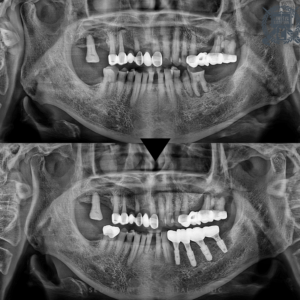

25.06.07

처음 내원하셨을 당시의 파노라마 방사선 촬영한 모습입니다. 치아상실과 뿌리만 남은 치아들, 치아우식, 치주질환으로 전반적으로 좋지못한 상태였습니다.

뿌리만 남은 치아의 상태가 매우 좋지 않아서 다시 살려서 사용하시기 어려운 상태였습니다. 영도치과 서울화이트S치과는 차근차근 아래 치아들 부터 진행하는 것으로 계획하고, 파절치는 발치 후 임플란트를 식립, 상실한 치아가 있던 자리도 임플란트를 식립하고 신경치료와 보존치료로 살릴 수 있는 치아는 살려사 사용하실 수 있도록 게획을 세워드렸습니다.